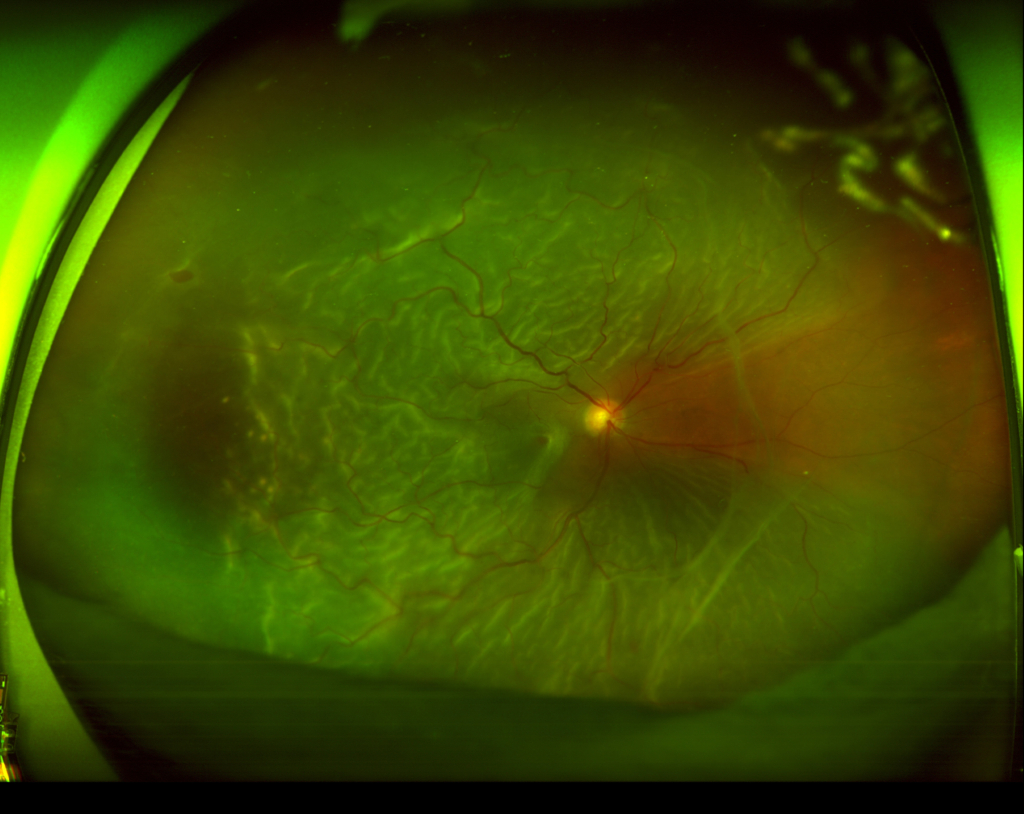

40歳 男性視力 右眼 0.02(1.2×-8.00) 左眼 0.04(1.2×-6.25=c-1.50A180°)主訴 検診で網膜色素変性症の疑いと指摘された。明らかな自覚症状なく、夜盲ははっきりしない。 金箔が剥げかかったような反射がみられる。 フラッシュERGで、減弱した...